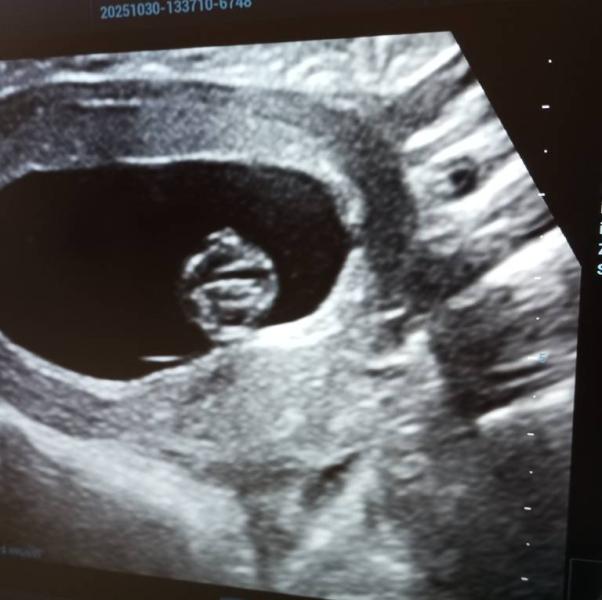

Сфотографировать экран монитора мне разрешили, но малыш в экране был головой вперёд и на головке будто рог😅😅😅 я конечно предполагаю что это он ручку на голове держит и так спит.

Да и оставила так экран после УЗИ где будто у ребёнка паталогия с рогом в голове. То на аборт отправляли, то экран УЗИ. Слова есть, но мало хорошие. 😅